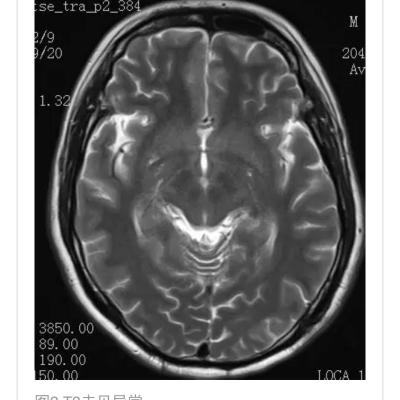

10月大婴儿,因癫痫持续状态就诊,2天前有发热和稀便。头颅MRI提示脑组织肿胀和累及丘脑,白质和背侧脑干的T2高信号病灶(图1)。丘脑病变在DWI和ADC上可见三层外观,伴有SWI上可见的局灶出血(图1-2)。 最终诊断:急性坏死性脑病 讨论 儿童急性坏死性脑病是一种爆发性脑病,主要累及婴幼儿。诱发因素包括病毒感染(流感病毒,轮状病毒,人类疱疹病毒6),免疫介导和遗传(RANBP2突变)。DWI和ADC上的三层表现和对称性丘脑受累具有特征性。